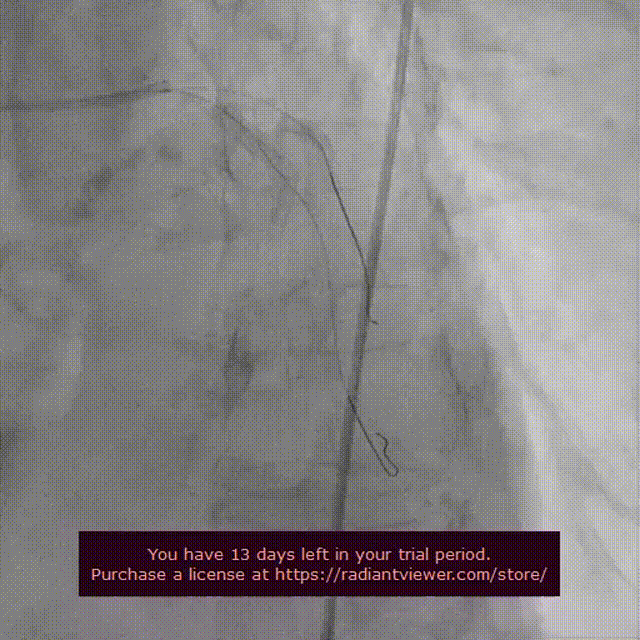

瓣膜第一次释放造影

起搏150次/分,VenusA-Plus®L26标准位快速释放,释放至三分之二处,造影发现瓣膜位置不佳,下滑严重,快速进行回收,重新定位释放,造影发现第二次释放位置良好。

瓣膜位置下滑进行回收

瓣膜第二次释放造影